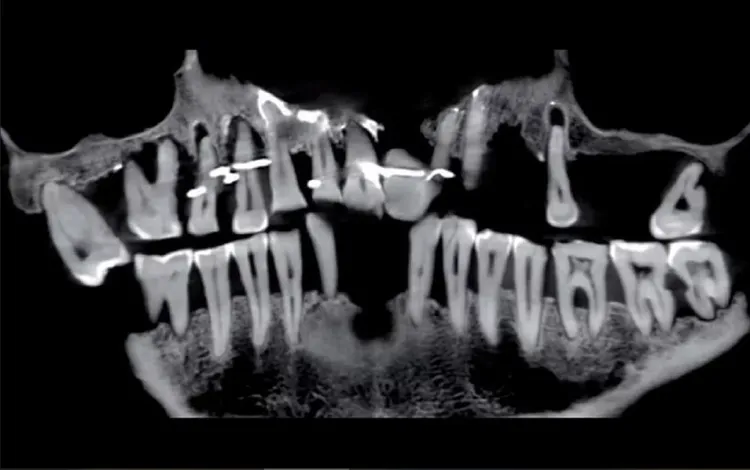

考古學家發現了一顆假牙,以及用於固定牙齒的結紮線,掃描顯示,女主角患有嚴重的牙周病,導致多顆牙齒鬆動。為防止牙齒掉落,她使用了細金線固定牙齒。

金線通常纏繞在達勒格的牙齒底部,靠近牙齦的位置。某些牙齒還被鑽孔以讓金線穿過,她還佩戴了一顆由象牙製成的假牙。

從X光照片可看到一些牙根已經搖搖欲墜。《考古雜誌》